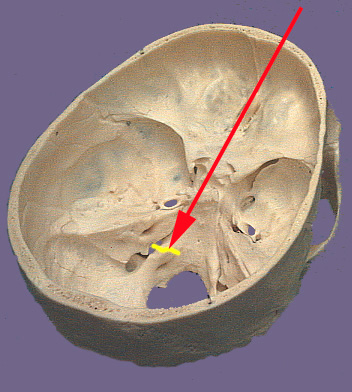

The glossopharyngeal nerve as its name suggests is related to the tongue and the pharynx. The ninth cranial nerve exits the brain stem as a the most rostral of a series of nerve rootlets that protrude between the olive and inferior cerebellar peduncle. These nerve rootlets come together to form the ninth cranial nerve and leave the skull through the jugular foramen. The tympanic nerve is a branch that is occurs prior to exit the skull. The visceromotor or parasympathetic part of the ninth nerve originate in the inferior salivatory nucleus. Nerve fibers from this nucleus join the other components of the ninth nerve during their exit from the brain stem. They branch in the cranium as the tympanic nerve. The tympanic nerve exits the jugular foramen and passes by the inferior glossopharyngeal ganglion. It re-enters the skull through the inferior tympanic canaliculus and reaches the tympanic cavity where it forms a plexus in the middle ear cavity. The nerve travels from this plexus through a canal and out into the middle cranial fossa adjacent to the exit of the greater petrosal nerve. It is here the nerve becomes the lesser petrosal nerve. The lesser petrosal nerve exits the cranium via the foramen ovali and synapses in the otic ganglion. The otic ganglion provides nerve fibers that innervate and control the parotid gland, an important salivary gland. The branchial motor component supplies the stylopharyngeas muscle which elevates the pharynx during swallowing and talking. In the jugular foramen are two sensory ganglion connected to the ninth cranial nerve: the superior and inferior glossopharyngeal ganglia. General sensory components from the skin of the external ear, inner surface of the tympanic membrane, posterior one-third of the tongue and the upper pharynx join either the superior or inferior glossopharyngeal ganglia. The ganglia send central processes into the brain stem which terminate in the caudal part of the spinal trigeminal nucleus. Visceral sensory nerve fibers originate from the carotid body (oxygen tension measurement) and carotid sinus (blood pressure changes). The visceral sensory nerve components connect to the inferior glossopharngeal ganglion. The central process extend from the ganglion and enter the brain stem to terminate in the nucleus solitarius. Taste from the posterior one-third of the tongue travels via nerve fibers that enter the inferior glossopharnygeal ganglion. The central process that carry this special sense travel through the jugular foramen and enter the brain stem. They terminate in the rostral part of the nucleus solitarius (gustatory nucleus).